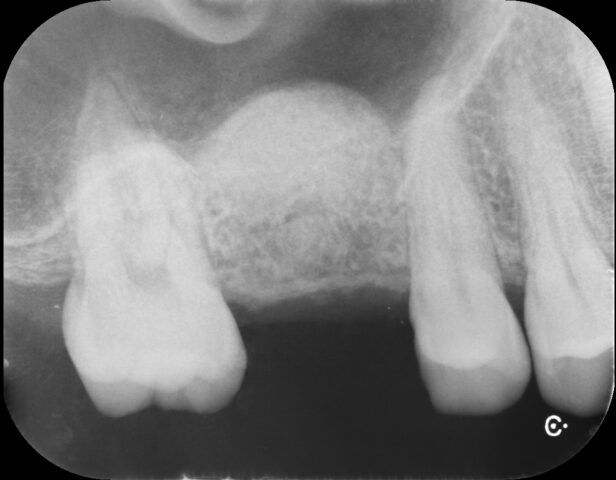

施術後のレントゲン写真 - ※手前の歯の根の位置を目安にするとかなりの量が挙上されていることがわかります。